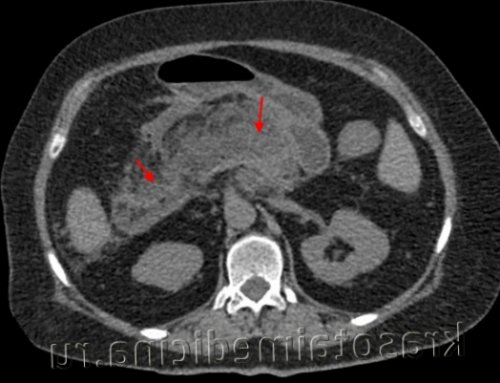

в брюшной полости к нескольким системам: пищеварительной и эндокринной. Основная функция — продукция ферментов и При тяжелой форме применяют октапептиды, селективно угнетающие панкреатическую секрецию, проводят интенсивную терапию для поддержания АД, стабилизации метаболических нарушений. Пациентам с установленной этиологией панкреатита показано лечение основного заболевания. При остром панкреонекрозе может выполняться некрэктомия поджелудочной железы, оментобурсостомия. При стойких болях, связанных с наличием кистозных образований, производится удаление ложных кист поджелудочной железы или марсупиализация истинных кист.• Обезболивающие препараты. Обычно используют ненаркотические анальгетики, которые при наличии спастических дискинезий дополняют миотропными спазмолитиками. При интенсивном болевом синдроме показана эпидуральная блокада, введение наркотиков.КТ органов брюшной полости. Панкреатит (в области хвоста поджелудочной железы) с наличием отека ее паренхимы, жидкостного содержимого вблизи ее края, на фоне утолщение фасции Героты слева• Исследование панкреатических ферментов в крови. Повышение уровня альфа-амилазы в 3-4 раза (при норме до 50 Ед/л) в первые сутки указывает на острый процесс или обострение хронического воспаления. С 4 суток проводят измерение уровня липазы — диагностически значимо двукратное увеличение показателя.Патогномоничным признаком острого панкреатита является триада Мондора — вздутие живота, боль и рвота. Болевые ощущения возникают внезапно, они очень интенсивны, иногда приводят к потере сознания. Боль опоясывающая, рвота многократная, не приносит облегчения. Для острого воспаления типично быстрое ухудшения общего состояния больного: выявляется тахикардия и резкое снижение АД, усиленная потливость, бледность кожных покровов.